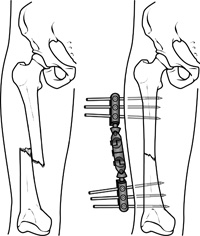

Nails or RodsIn some fractures of the long bones the best way to hold the bone pieces together is by inserting a rod or nail through the hollow center of the bone that normally contains some marrow. Screws at each end of the rod are used to keep the fracture from shortening or rotating, and also hold the rod in place until the fracture has healed. Rods and screws may be left in the bone after healing is complete. This is the method used to treat the majority of fractures in the femur (thighbone) and tibia (shinbone).

External FixatorsAn external fixator acts as a stabilizing frame to hold the broken bones in proper position. In an external fixator, metal pins or screws are placed into the bone through small incisions into the skin and muscle. The pins and screws are attached to a bar outside the skin. Because pins are inserted into bone, external fixators differ from casts and splints which rely solely on external support.

External fixation is often used to hold the bones together temporarily when the skin and muscles have been injured.